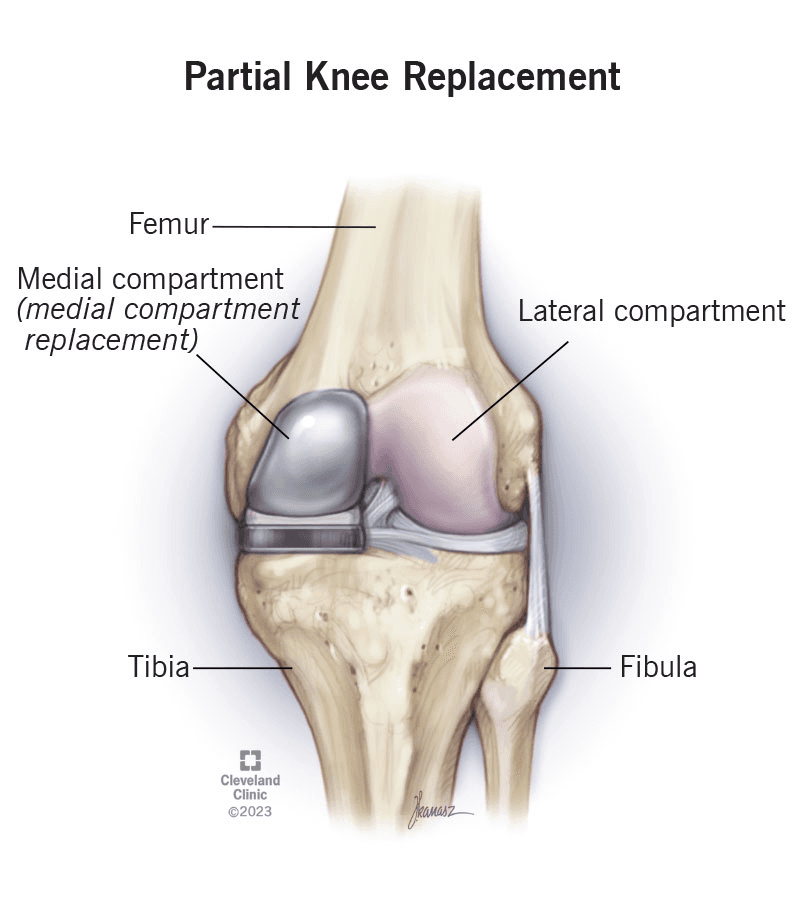

Advanced Technology

Robotic knee replacement & digital dental implant planning.

Before

Before After

AfterKnee Replacement Recovery

| Knee Replacement | $5200 | $18000 | $15000 | $16000 | $15500 | $14500 | $13000 | $9000 |